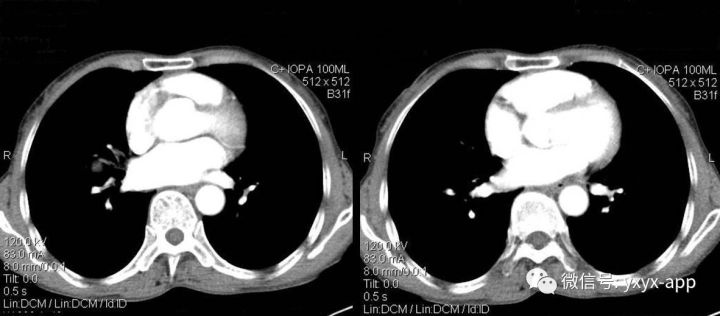

肚肚丫头:右肺门结节影,边界清,密度尚均匀,增强扫描动脉期,病变呈轻度强化,静脉期强化明显(与血管相当),病灶部分与支气管相贴。纵隔未见肿大的淋巴结。考虑与血管相关的良性病变可能。1.硬化性血管瘤;2. 巨淋巴结增生不除外

2.CT平扫病灶密度较均匀,与肌肉密度相近,多数PSH增强扫描动脉期有所强化,静脉期及延迟期持续均匀强化;少数为不均匀强化。较小病灶以血管瘤型和乳头型为主,强化较明显且均匀;随着病灶增大,实体型和硬化型成分逐渐增多,强化程度随之减低且不均匀。

3.相对特殊征象有①空气新月征:少数PSH表现为病灶边缘新月形或半月形无肺纹理区;②贴边血管征:表现为边缘明显强化的点状血管断面,动脉期强化明显且先于病灶本身强化,与肺动脉强化程度相近;③尾征:表现为瘤边缘尾状突起且多位于病灶近端靠近肺门一侧。

本例特点为①病灶为圆形,小于3cm,边缘光滑,无钙化及囊变;②肿瘤增强扫描为动脉期有所强化,静脉期持续均匀强化,与同层肺动脉相近;③相对特殊征象:仅见动脉期贴边血管征,未见空气新月征及尾征。本例主要要与肺无脂肪和钙化的错构瘤鉴别,以及炎性肌纤维母细胞瘤鉴别,后两者均不具有持续均匀强化的特点,可做鉴别。而巨淋巴结增生症动脉期明显强化,静脉期回落,与本例强化时相不符。